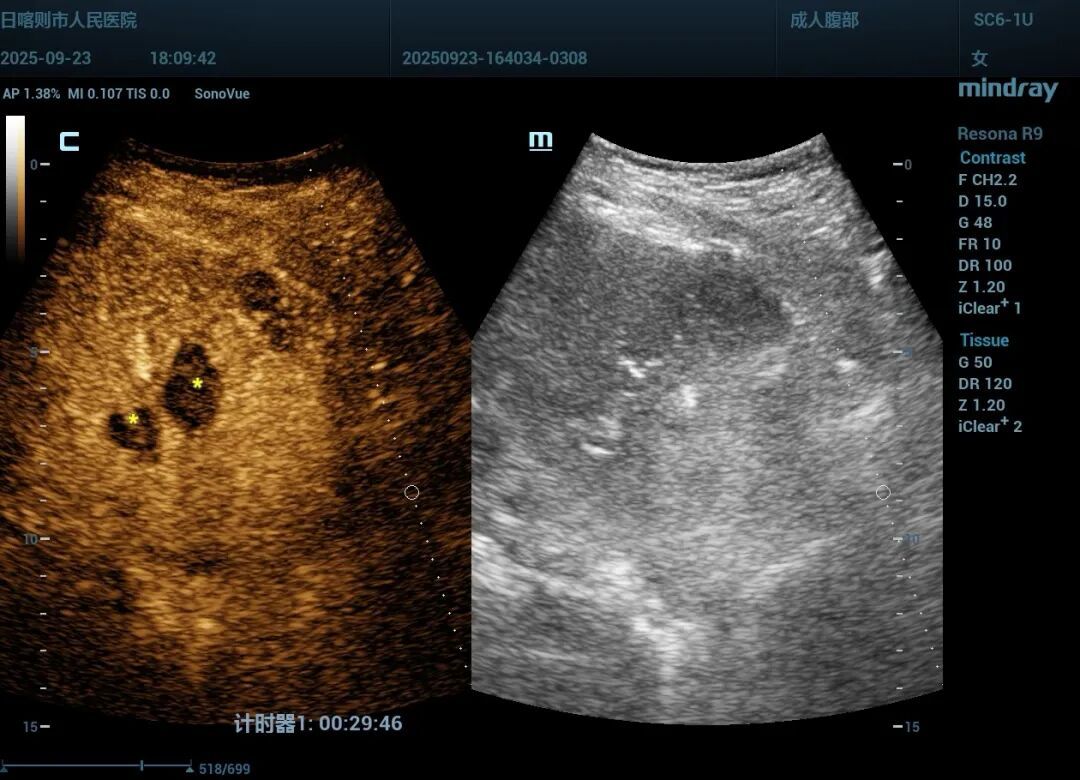

消融前超声造影定位病灶位置(左);消融后造影复查病灶完全破坏呈“黑洞征”(右)